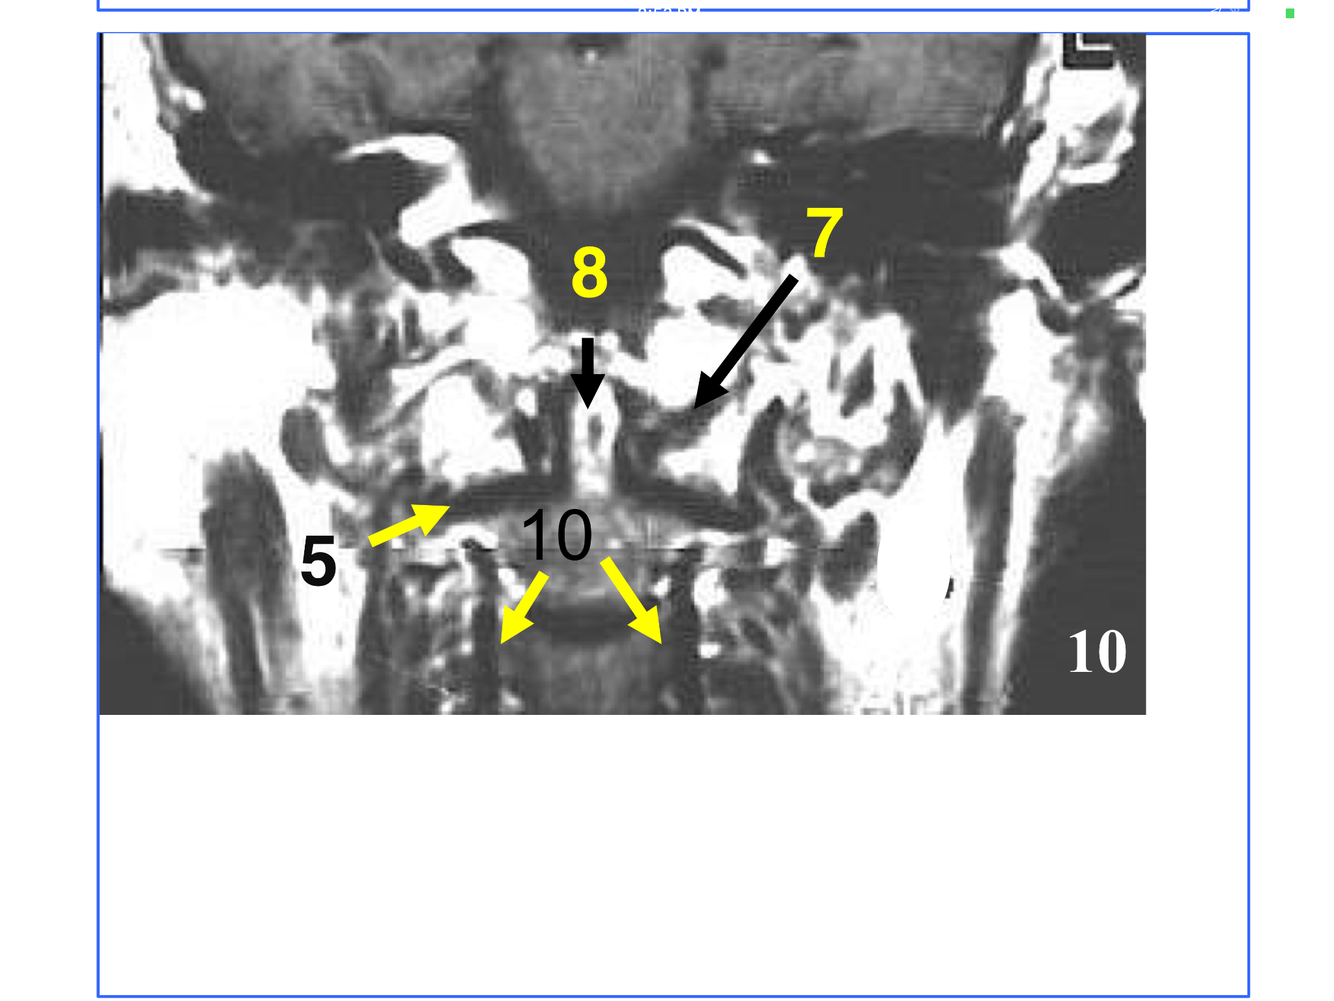

**10. Rt & Lt vertebral arteries**